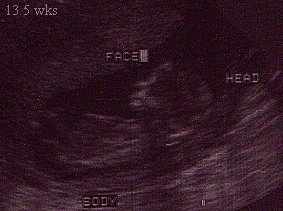

13½ weeks

Above are two sonogram pics of Michael Aaron I wanted to include these to show that there really IS a baby in there not just a blob :-)